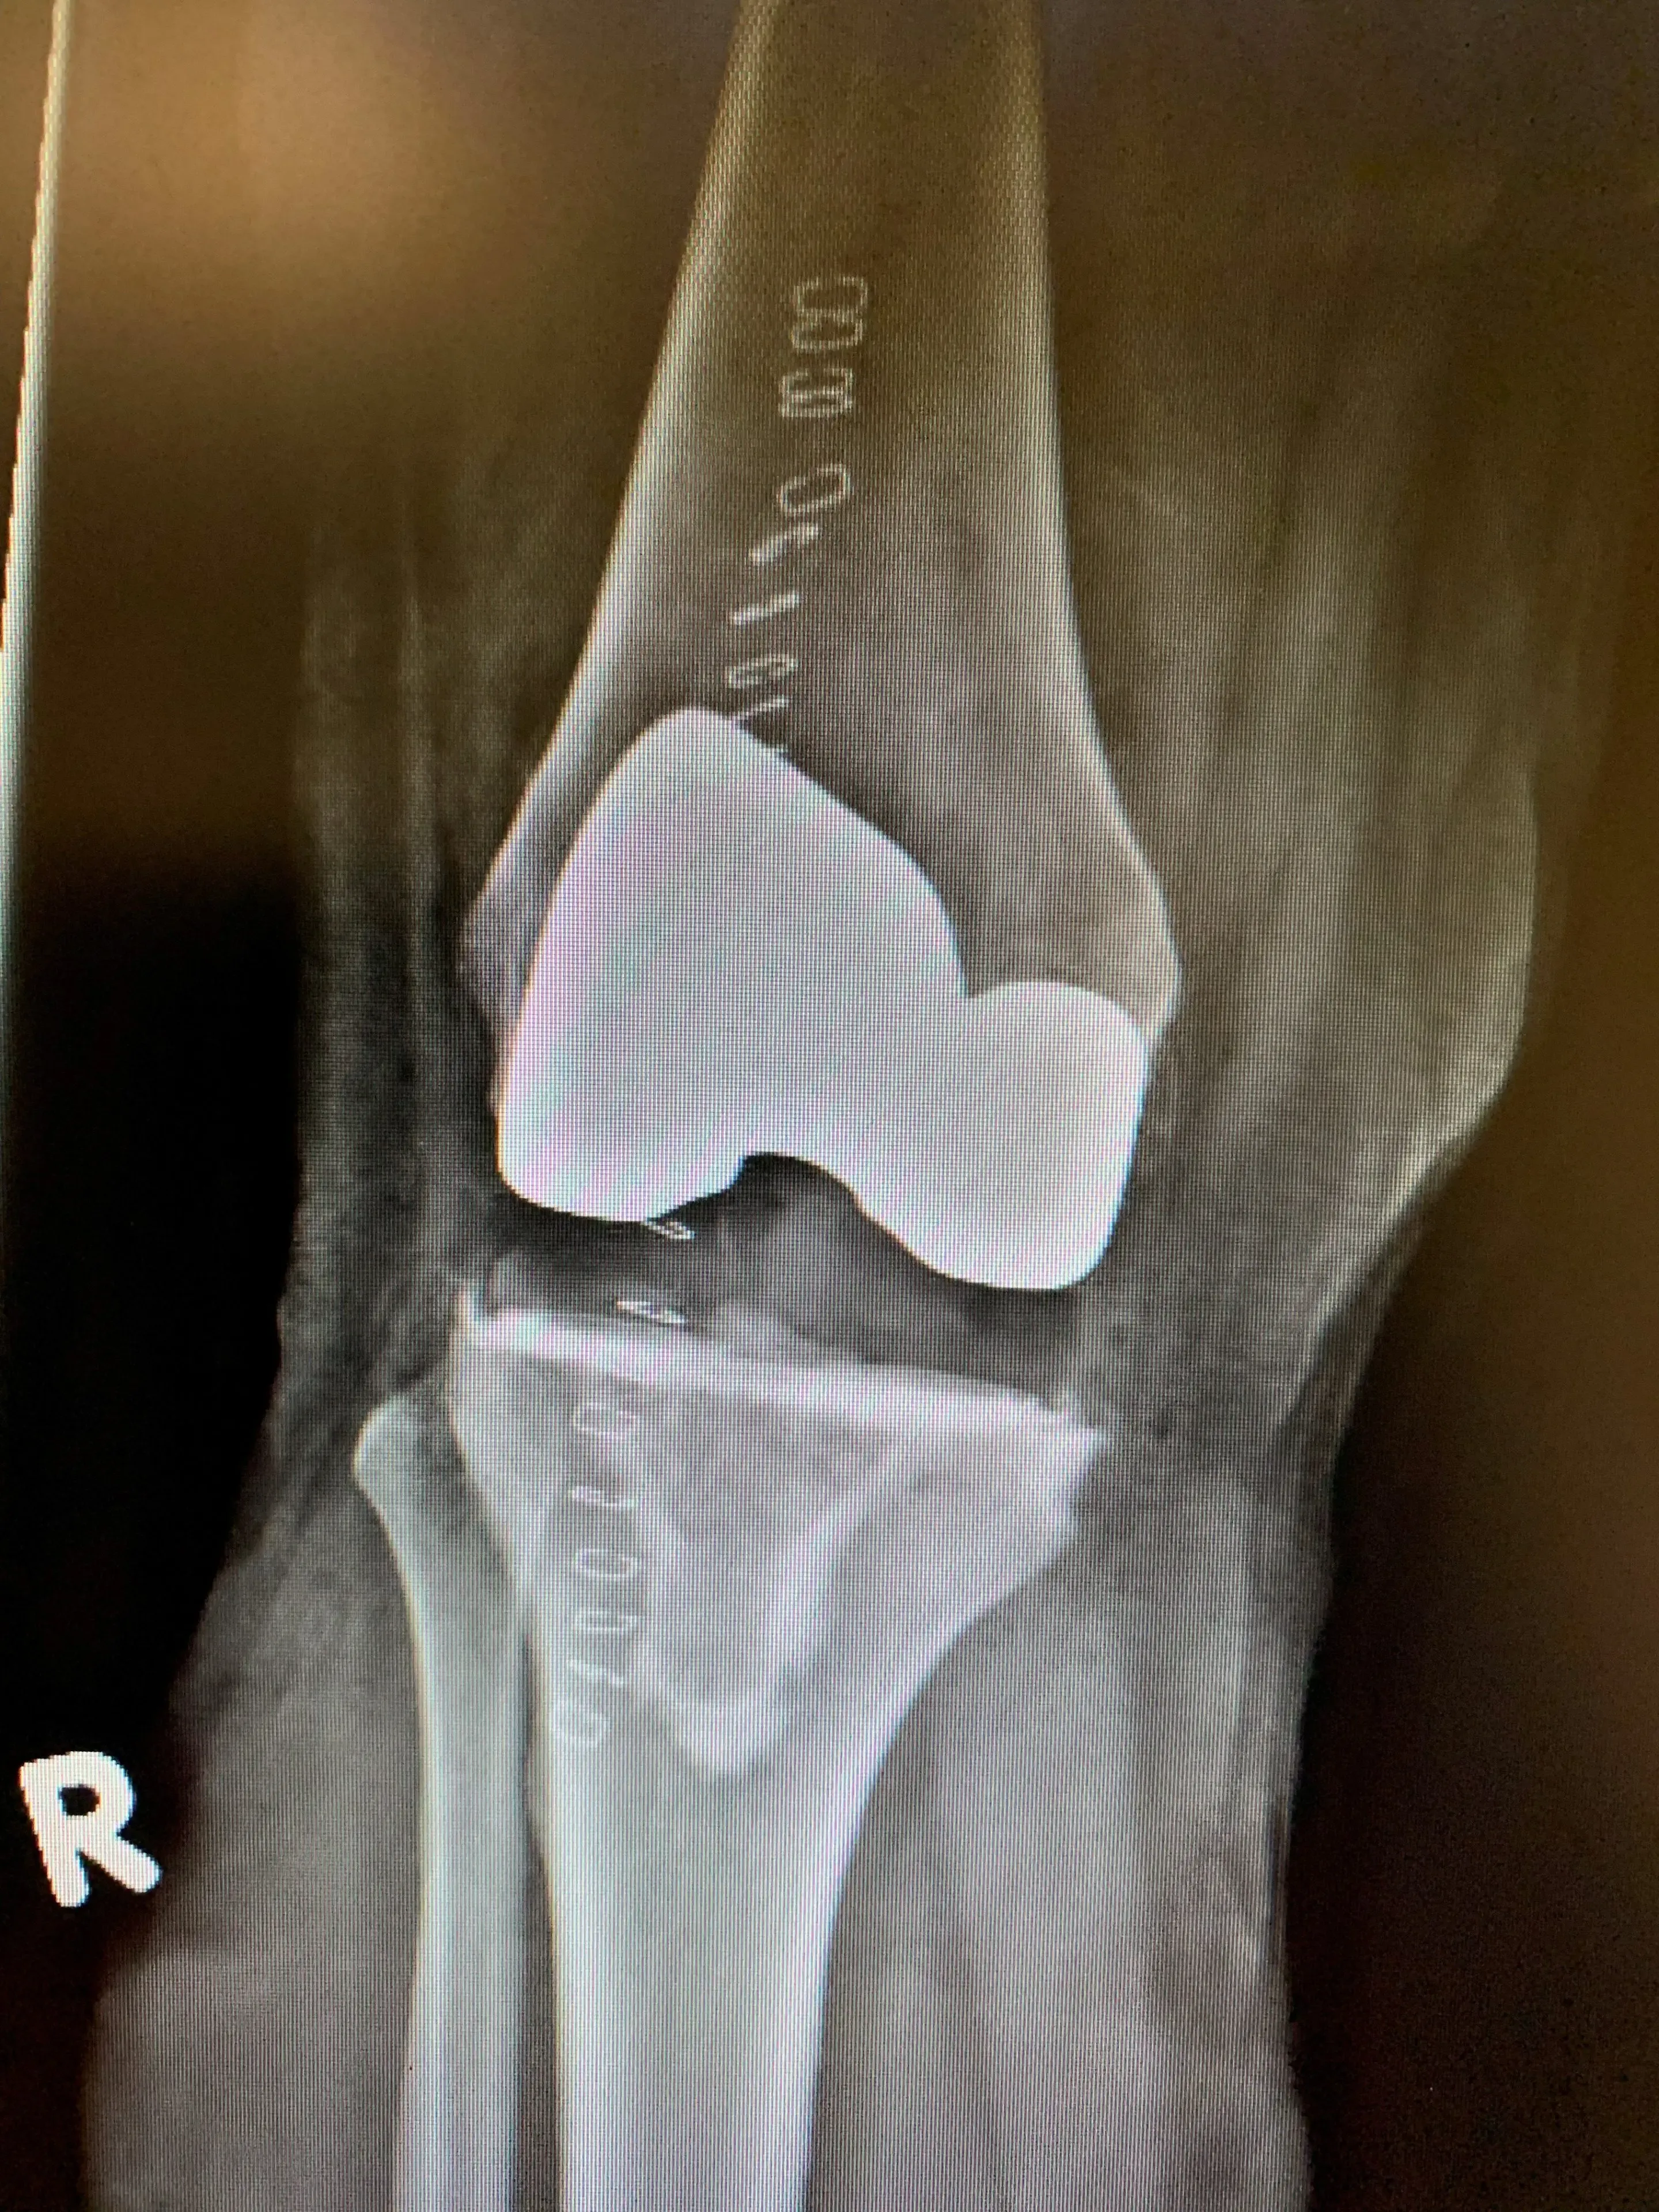

We ultimately deemed him to be a candidate for knee arthroplasty surgery, and were also able to offer him Patient-specific knee Instrumentation surgery. This involved sending Mr. TF for a knee MRI that he otherwise would not have received if he were receiving standard knee instrumentation surgery. This scan was then sent to the implant company who then used it to create instruments for use during the procedure that were specific to Mr. TF’s knee anatomy.

These custom instruments allowed us to make specific bone cuts that matched the inner surface of the knee prosthesis. The advantage of these cuts is that they would result in minimal amounts of bone being removed to complete the procedure. The steps in the procedure itself do not change, and the components implanted match the outer surface geometry of standard implants in order to replicate optimized biomechanics.

Mr. TF recovered very well from his procedure, and was discharged from hospital the day after his surgery. He is doing well 1 year after his surgery, and is pleased to have had the opportunity to have benefited from instrumentation specific to his anatomy, and would recommend it to anyone who has a similar opportunity.

Post-op